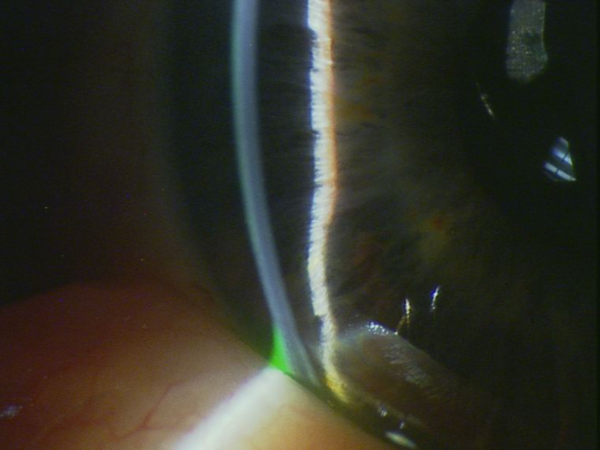

Cristallin clair